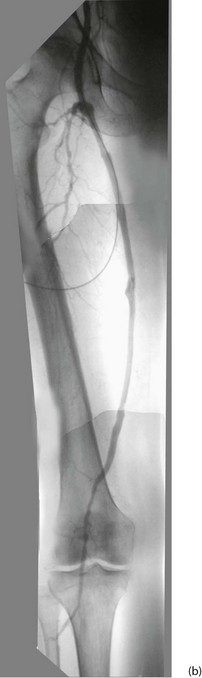

Arteriography (see Ch. 5): Arteriography should be reserved for patients thought to require angioplasty or reconstructive surgery. It maps the arterial system (see Fig. 41.1), showing sites and severity of stenoses and occlusions, the quality of inflow (arteries feeding the area of concern) and the runoff (arteries beyond the main obstruction, see Fig. 41.2). Arteriography is sometimes used wrongly by non-specialists to assess chronic arterial insufficiency but it cannot measure blood flow to the tissues or dynamic circulatory responses to exercise; it helps only with the mechanics of revascularisation. Traditional arteriography is performed via direct arterial puncture but carries risks of vessel trauma and high doses of contrast aggravating chronic renal impairment. It is being replaced by less invasive CT and MR angiography which use lower doses of intravenous contrast media.

Fig. 41.2 Arteriograms comparing the normal with typical patterns of arterial obstruction affecting the lower limbs

(a) This magnetic resonance angiogram is entirely normal, showing smooth, regular arterial walls, all branches intact and three normal infra-inguinal arteries below knee on each side. (b) This composite subtraction arteriogram was performed because the patient suffered bilateral severe claudication. The aorta is irregular and narrowed by atherosclerosis from above the renal arteries to the bifurcation. The common, internal and proximal external iliacs are normal and smooth but the right external iliac is occluded and the left stenosed. Both profunda femoris arteries are occluded. The superficial femoral arteries are both diseased and occluded distally. On the left side, collaterals are visible around the knee area. The infrageniculate vessels are diseased on both sides with stenoses and occlusions. Reconstruction would have been extensive, difficult and risky, and hence conservative management alone was undertaken, in the absence of rest pain or tissue loss